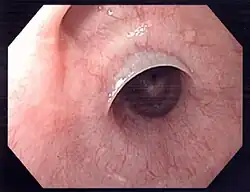

Web with "jet-phenomenon". Arrowhead on incomplete opening of the upper esophageal sphincter.

Web with "jet-phenomenon". Arrowhead on incomplete opening of the upper esophageal sphincter. -